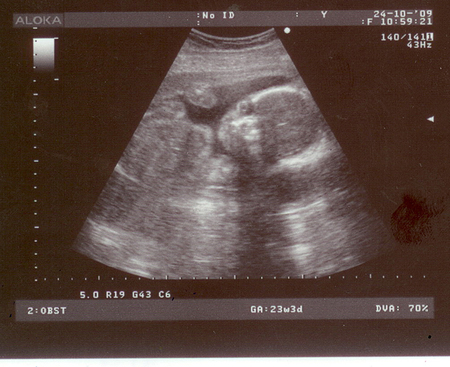

А здесь он машет. Правда не видно особо))

Папа называет его инопланетянин глазастый)))